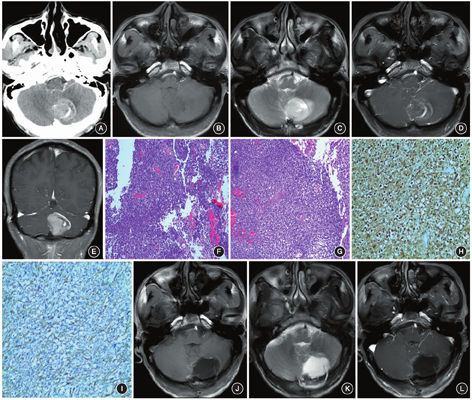

患者 男,60岁,因"头晕伴行走不稳10 d"入院,无头痛、视物旋转、意识障碍、恶心呕吐、四肢抽搐、发热等不适,体格检查和实验室检查均未见明显异常。头颅CT增强扫描显示左侧小脑半球存在占位性病变,大小为3.5 cm×2.8 cm(图1A);头颅MRI也显示左侧小脑半球存在占位性病变,在T1加权成像(T1WI)上呈等低信号(图1B),T2加权成像(T2WI)上呈等稍高信号,周围可见片状水肿高信号影(图1C),增强扫描显示病变明显渐进性强化,边缘可见增粗的血管影,小脑蚓部及第四脑室略受压(图1D,E)。术前诊断为后颅窝占位,脑膜瘤可能大。手术操作:取正中长约8 cm直切口,切开枕颈部肌肉,显露枕下颅骨。钻2个骨孔,用铣刀铣开颅骨,骨窗大小约为5 cm×4 cm。悬吊硬脑膜止血,涂骨腊止血。硬脑膜张力稍高。在显微镜下操作,切开硬脑膜,即见淡黄色肿瘤,分块切除。术中可见肿瘤质软、边界不清且血供丰富。术中切除的部分肿瘤组织标本行快速冰冻病理学检查,结果显示肿瘤细胞呈多形性,易见核分裂,还可见坏死组织,考虑为脑胶质瘤。因此,术中扩大切除范围,切除肿瘤周围边缘的正常小脑组织。最后采用人工硬脑膜修补缺损的硬膜,骨瓣回纳,颅骨锁钉固定,皮瓣下放置3 mm引流管。术后3 d,患者意识清楚,精神状态好,对答正确,定向力正常,双侧瞳孔等大、等圆,直径为2.5 mm,对光反应灵敏,偶有头晕,但无其他明显的不适症状;Karnofsky功能状态评分(Karnofsky performance scale,KPS)为80分。术后行病理学检查,HE染色可见肿瘤细胞排列密集,多形性,异型明显,核分裂易见,并可见病理性核分裂象,内皮细胞增生,可见较多不成熟的血管增生,另可见坏死组织;免疫组织化学染色结果显示,胶质纤维酸性蛋白(glial fibrillary acidic protein,GFAP)、S-100、波形蛋白(Vimentin)、CD34均呈阳性表达,p53呈少数阳性表达,而AE1/3、上皮细胞抗原(epithelial membrane antigen,EMA)均呈阴性表达;Ki-67增殖指数为40%;分子病理学检查结果显示,突变型异柠檬酸脱氢酶1(isocitrate dehydro-genase 1,IDH1)表达阴性,O6-甲基鸟嘌呤-DNA-甲基转移酶(O6-methylguanine-DNA methyltransferase,MGMT)启动子甲基化,且1p/19q未缺失;最后诊断为胶质母细胞瘤,为WHO Ⅳ级(图1F~I)。术后患者辅以放疗,同步应用替莫唑胺(75 mg/m2)进行化疗。术后1年复查头颅MRI,显示术区存在局限性积液,但未见强化征象(图1J~L)。

GBM在影像学上呈膨胀性、浸润性生长,常累及多个脑叶,并侵犯大脑深部结构;当发生于小脑幕上时,可跨越胼胝体并侵袭大脑对侧。GBM的侵袭性较强,常伴有坏死、出血,增强扫描时常呈蜂房样或花环样强化,部分可见壁结节,水肿和占位效应较显著[5]。文献报道,发生在小脑半球的GBM可表现为:(1)不规则的环状强化,与小脑幕上GBM相似;(2)均匀的片状或结节状强化,无坏死,类似恶性淋巴瘤和转移癌;(3)在T2WI上呈平行线性条纹的高信号影(即"虎纹"外观)[6]。本例患者发生在左侧小脑半球,增强扫描呈明显的渐进性强化,局部存在少许囊性坏死,边缘可见增粗的血管影,与小脑幕上GBM明显不同,属于部位罕见且影像学上不典型的GBM,易被误诊为脑膜瘤。脑膜瘤起源于蛛网膜颗粒细胞,发生于硬脑膜的内表面,多数肿瘤的宽基底部位与硬脑膜相连,增强扫描呈现显著强化,周围可见"脑膜尾征"。